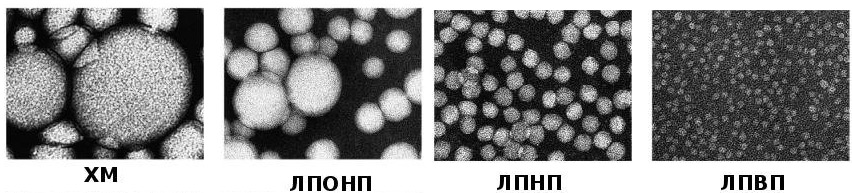

Липопротеины плазмы крови классифицируются по плотности, что определяется методом ультрацентрифугирования. Чем больше липидов в молекуле липопротеина, тем ниже его плотность. Выделяют несколько типов: ЛПОНП, ЛПНП, ЛПВП и хиломикроны. Эта классификация считается наиболее точной и разработана с использованием высокоточного метода ультрацентрифугирования.

Липопротеины также различаются по размерам. Наибольшими являются молекулы хиломикронов, затем идут ЛПОНП, ЛПСП, ЛПНП и ЛПВП, уменьшаясь по размеру.

Эти липопротеины являются крупнейшими после хиломикронов. Более 50% их состава составляют триглицериды, а также в них содержится небольшое количество холестерина. При повышенном уровне ЛПОНП в крови она может стать мутной и приобрести молочный оттенок.

Хиломикроны отсутствуют в крови здорового человека и появляются только при нарушениях липидного обмена. Эти молекулы образуются в эпителиальных клетках слизистой оболочки тонкого кишечника. Их основная функция — транспортировка экзогенных жиров из кишечника в периферические ткани и печень. Основную часть переносимых жиров составляют триглицериды, а также фосфолипиды и холестерин. В печени триглицериды расщепляются на жирные кислоты под действием ферментов. Часть из них направляется в мышцы и жировую ткань, а другая связывается с альбуминами в крови.